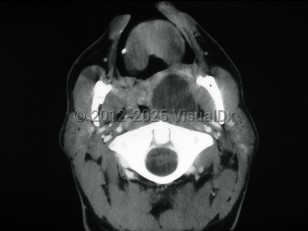

Peritonsillar abscess, also known as quinsy, is a deep neck space infection characterized by a collection of pus in the peritonsillar space.

Patients present with a muffled voice, fever, sore throat, and dysphagia. There is deviation of the uvula to the unaffected side. Trismus and otalgia may be present. This infection usually affects young adults, but all ages can be affected. Older adults may have subtler symptoms. Laboratory findings include leukocytosis. Treatment consists of antibiotic therapy and surgical drainage.

Complications of this infection include airway obstruction or extension of the infection into contiguous spaces in the neck.